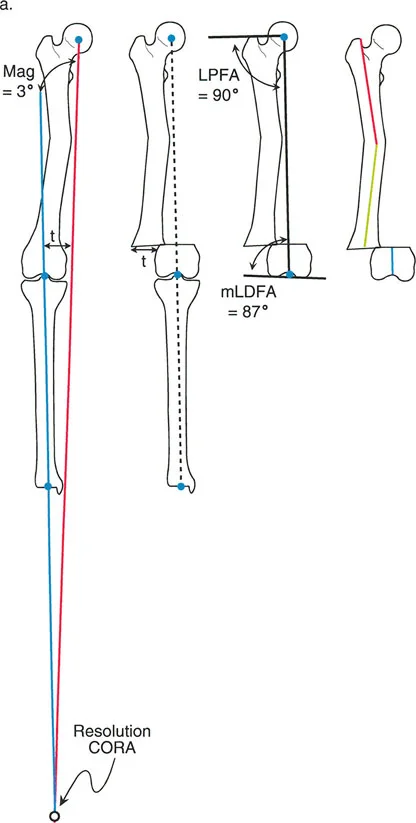

إن فهم العلاقة المكانية والخاصة بين الانحراف والانزياح هو حجر الزاوية في تصحيح تشوهات العظام الحديثة. لقد وضع الأستاذ الدكتور درور بالي، وهو رائد في هذا المجال، أسسًا للتحليل المنهجي لهذه التشوهات المركبة، معتمدًا على مبادئ هندسية صارمة، وتحديدًا تحديد مركز دوران الانحراف (CORA) وتقييم انحراف المحور الميكانيكي (MAD).

يهدف هذا الدليل الشامل إلى تبسيط هذه المفاهيم المعقدة، وتحويل النصوص الطبية المتخصصة إلى معلومات عالية الأهمية وقابلة للتطبيق سريريًا للمرضى وأسرهم. سنستكشف كيفية قياس هذه التشوهات بدقة، وكيف تتفاعل لتؤثر على المحور الميكانيكي (تأثيرات تعويضية مقابل تراكمية)، وكيفية تحليل تشوهات الانحراف-الانزياح من النوع الأول (التي تحدث في نفس المستوى) للعثور على القمة الحقيقية للتشوه.

بمجرد الحصول على صور التصوير الشعاعي عالية الجودة، يقوم الأستاذ الدكتور محمد هطيف بإجراء تحليل هندسي دقيق باستخدام مبادئ الدكتور بالي:

- رسم المحاور: يتم رسم خطوط المحور الوسطي للعظم (mid-diaphyseal axis lines) للأجزاء القريبة والبعيدة من العظم المصاب على كل من الأشعة السينية الأمامية الخلفية والجانبية.

- تحديد مركز دوران الانحراف (CORA) أو نقطة الانحراف-الانزياح (a-t point): هذه هي النقطة التي تتقاطع عندها خطوط المحور، وتُعد "القمة الحقيقية" للتشوه. تحديدها بدقة أمر بالغ الأهمية لتخطيط مكان قطع العظم.

- قياس الانحراف والانزياح: تُستخدم قياسات دقيقة لتحديد حجم الزاوية (الانحراف) ومقدار التحرك الجانبي (الانزياح).

- تقييم انحراف المحور الميكانيكي (MAD): يُحسب مدى انحراف المحور الميكانيكي عن مركزه الطبيعي في الركبة.